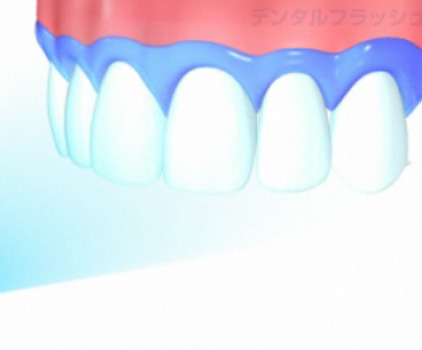

ラバーダム防湿について

お口の中はばい菌だらけです。根の治療をするにあたり根の中にばい菌をできるだけ入れないように配慮が必要です。

金属の金具とゴムのマスクを使ってばい菌の侵入を最小限にするのがラバーダム防湿です。

日本ではあまりなじみのない方法ですが、質の高い歯科治療には必要になります。

なぜラバーダムが必要か?

■根管治療の成功率

ラバーダム(ゴムのマスク)を使用した場合:約90%(初回治療時)

ラバーダム(ゴムのマスク)を使用しない場合:約50%以下(初回治療時)

※初回治療時にラバーダムを使用した場合の、再治療時の成功率は約60%。

ラバーダムの使用により治療の予後が向上します。